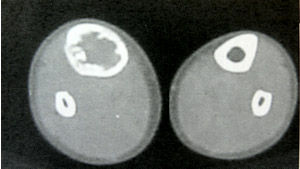

二、X線上,病灶的密度常有差異,取決於病理成分,病灶如主要為纖維組織常表現為囊狀透光區;如主要為砂礫樣鈣化新生骨者常呈磨砂玻璃狀;如新生骨鈣化較多時則表現為一片明顯的增白區。每一病灶,可以上述表現按不同比例組合出現。

骨纖維異常增殖症1、囊性

(1)囊性:以四肢骨多見。

(2)表現為囊狀透光區,皮質變薄,骨幹可有膨脹,囊內有磨玻璃樣改變及鈣化。

(3)單囊可發展成多囊,囊內有粗大的骨小梁,邊緣可有硬化 。

3、位於長、短管狀骨和肋骨的病灶多發生於骨幹或骨骺端,病骨膨脹而變粗大,常呈單房透明或磨砂玻璃狀,範圍較大,其中可有緻密骨嵴沿骨長軸方向走行向內凸出,使病灶呈不完全的分房狀如“絲瓜囊”。有時在病灶內可見或大或小的片狀鈣化影。

4、位於顱底骨和面骨的病灶以硬化型多見,表現為骨密度均勻增高,骨質增厚,與正常骨分界可清楚不清。